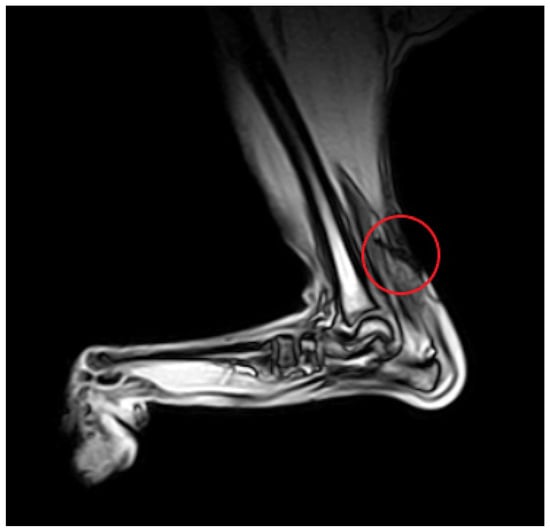

Magnetic resonance imaging allows for the visualization of tendons and adjacent soft tissue structures in high resolution, multiplanar images (Figure 5). A case report by Lin et al. [47] is the first and only description of the use of MRI in the diagnosis of an Achilles tendon injury in a dog. The tissue at the site of the tendon tear is homogeneous and hyperintense in T2-weighted images, which is similar to previously reported findings in human medicine [48,49,50,51]. The authors also observed the thinning and displacement of tendon fragments and foci of post-contrast enhancement at the site of the injury [47].

Figure 5. MRI GE T1-weighted image of a partial Achilles tendon rupture (circle).